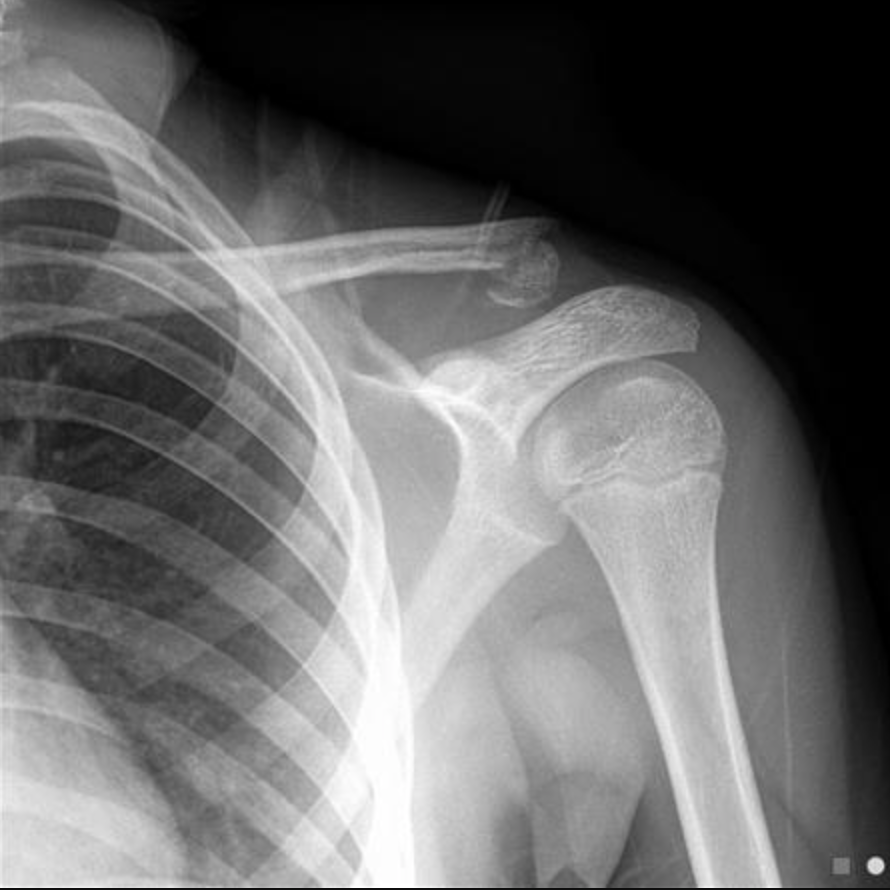

60F with shoulder trauma~fell from standing with impact to R shoulder

A

Transverse fractures of the surgical neck (red line)

Fracture line (yellow) causing separation of the greater tubercle

there is only minor displacement with moderate impaction and angulation (~30 degrees), with the glenohumeral joint remaining enlocated.

This would be considered a one-part fracture, as although both a greater tuberosity and surgical neck of humerus fracture are present neither are significantly displaced (<1cm) nor are they significantly angulated (<45 degrees).

How well did you know this?